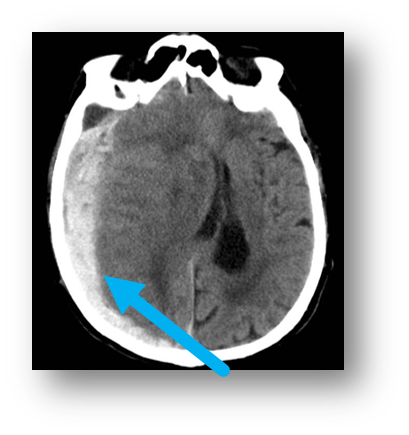

Q

subarachnoid hemorrhage